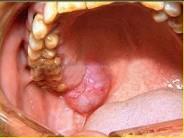

问题 以下关于黏液表皮样癌(如图)的叙述中,哪项是错误的 ( )

选项 A.高分化黏液表皮样癌很少发生颈淋巴结转移 B.女性多于男性,发生于腮腺者居多 C.低分化黏液表皮样癌淋巴结转移率高 D.高分化和低分化者均应作选择性颈清 E.高分化黏液表皮样癌较低分化黏液表皮样癌常见

答案 D